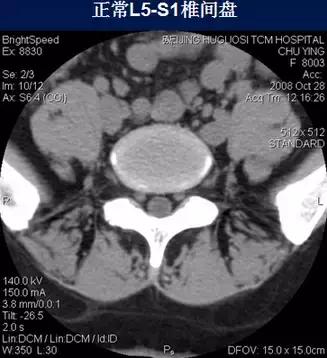

常规腰椎CT扫描层面

常规腰椎CT扫描L3-S1段,分为

(1)椎体层面(骨窗):观察椎体、附件骨质。

(2)椎间盘层面(软组织窗):观察椎间盘、硬膜囊、神经根、韧带等软组织。